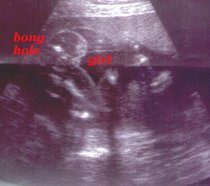

In this one you can see I'm a girl.

Another girl shot.

Another shot of my privates.